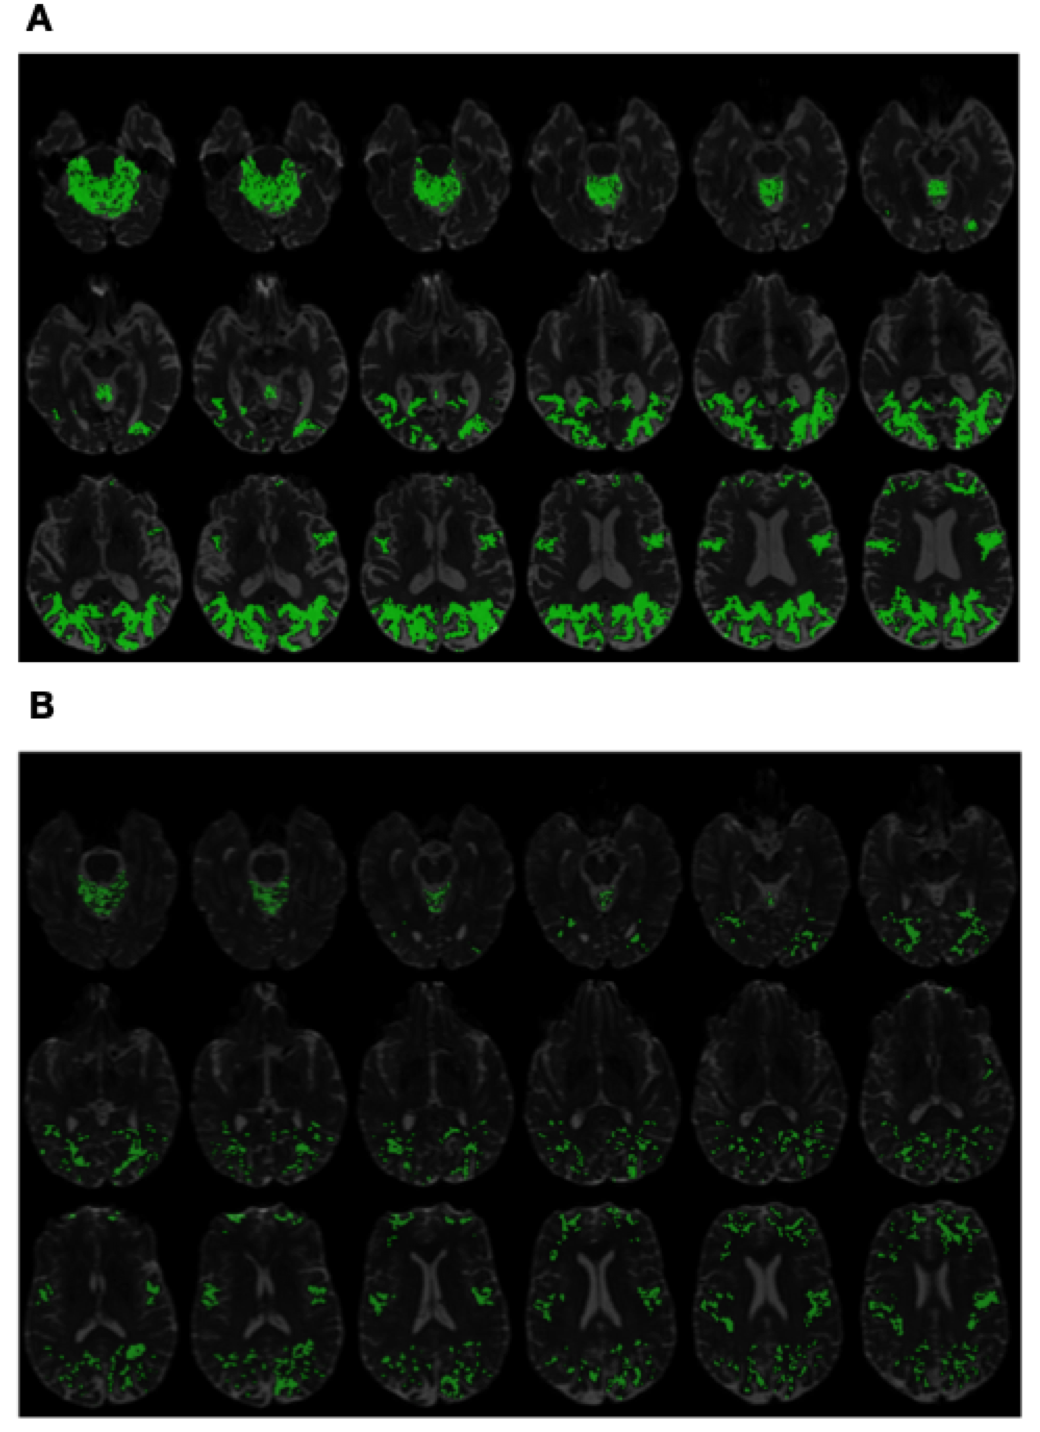

Refer to caption

Figure 4. (Subplot A) PSIC values of an AD subject superimposed on structural MRI scans. (Subplot B) PSIC values of a CN subject superimposed on structural MRI scans.

Finally, Fig. 4 and Fig. 5 exemplify the use of PSIC in its capacity as imaging contrast. It should be emphasized that, as opposed to diffusion metrics, the values of PSIC have no physiological interpretation. Instead, PSIC could be viewed as a pathology-specific risk indicator, whose higher values reflect a higher probability of the brain to be affected by the disease. This property of PSIC is evident in Subplots A of Fig. 4 and Fig. 5 which show the PSIC-enhanced structural scans of two AD subjects. In this case, the spatial distribution of PSIC values appears to be both intense and spatially pervasive. On the other hand, Subplots B of the same figures show results for two CN subjects. One can see that, in this case, the magnitude and spatial spread of PSIC appear to be much more “diluted”.

Due to the preliminary nature of the present paper, an in-detail exploration of the spatial characteristics of PSIC as well as its correlation with underlying brain anatomy and its possible etiological explanations are left beyond the scope of this report. However, in view of the empirical evidence provided by Fig. 4 and Fig. 5, it is reasonable to expect the proposed contrast mechanism to be “worth a thousand words”, both as an adjunct to establishing a confident diagnosis and as a means to facilitate post hoc discoveries.